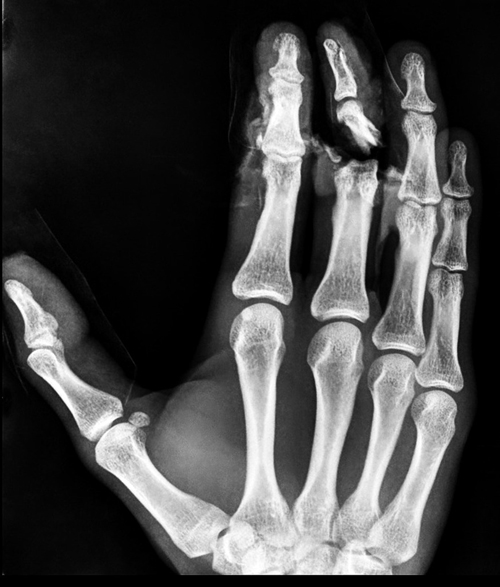

4 -شکستگی بندهای انگشتان:

4-1: مقدمه: شکستگی میتواند در هر کدام از سه بند انگشت ایجاد شود. هر انگشت سه مفصل دارد (البته بجز انگشت شست که دو بند دارد) و خط شکستگی در هر کدام از این مفاصل وارد شود مهم و خطرناک است. این شکستگی ها باید بسیار به دقت جااندازی شوند تا بدون جابجایی جوش بخورند وگرنه در صورت بدجوش خوردن میتوانند در دراز مدت موجب ساییدگی مفاصل شوند.

2-4: علایم شکستگی انگشتان و تشخیص آنها: دردی که با حرکت انگشت بدتر میشود. فشار دادن محل شکستگی درد را بیشتر میکند. همراه با درد، تورم انگشت، خونمردگی، عدم توانایی در حرکت دادن انگشت، کوتاه شدن و یا تغییر شکل انگشت میتواند از علائم دیگر شکستگی انگشت باشد. تشخیص قطعی با تصویربرداری رادیوگرافی است.

4-3: درمان شکستگی انگشتان: در موارد بروز این شکستگی ها، انتخاب نوع درمان به توسط پزشک و با در نظر گرفتن محل شکستگی، شکل شکستگی، شدت شکستگی، جابجا بودن یا نبودن آن و متغیرهای دیگر است. بسیاری از شکستگی های انگشت دست بدون جابجایی هستند. تنها درمان این شکستگی ها بستن انگشت شکسته شده به انگشت مجاور با یک چسب است.

اگر شکستگی همراه با جابجایی باشد پزشک معالج آنرا جااندازی کرده و در صورت پایدار بودن شکستگی، ممکن است گچ گیری انجام شود و مدت سه هفته طول بکشد. گاهی اوقات بعد از جااندازی بسته شکستگی پایدار نیست و قطعات شکسته شده مجددا جابجا میشوند که در این موارد قطعات شکسته با کمک پین های فلزی کنار هم تثبیت می گردند.

گاهی اوقات بند انتهایی انگشت ممکن است بدنبال اصابت جسم سخت مانند ضربه چکش یا گیر کردن انگشت لای در، خرد شود. در این موارد معمولا پوست انگشت زخمی میشود و یا ممکن است زیر ناخن خونریزی کرده و کبود شود و یا حتی ممکن است ناخن از بستر خود کنده شود. این شکستگی ها نیازی به بستن ندارند و خودبخود جوش میخورند. درمان در این موارد باید بیشتر معطوف به وضعیت آسیب پوست و بستر ناخن باشد . در مواردی که شکستگی انگشتان با عوارض عصبی و عروقی همراه باشد جراحی ضرورت می یابد. درصورت آسیب عروقی همراه، احساس سرد در نوک انگشتان خواهیدداشت و درصورت آسیب عصبی همراه، حس یا حرکت انگشت مختل می شود.